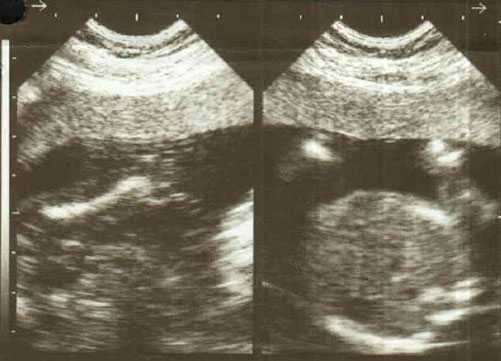

I am expecting a baby first time, below is my ultrasound images.

Please predict the gender of my baby. The ultra sound was done at 18th week.